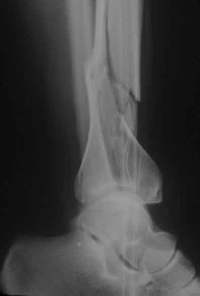

Unfallaufnahme (ap)

Offene Tibiafraktur Grad III